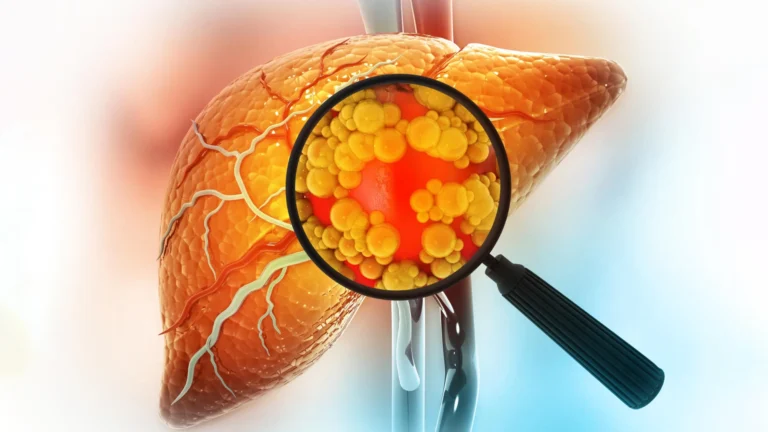

A cada segundo, inúmeras células no corpo humano se dividem para criar novas células. Este é um dos processos mais importantes na biologia e exige que milhares de moléculas trabalhem juntas com uma precisão incrível. Contudo, às vezes, esse processo apresenta falhas de maneiras inesperadas. Antes que uma célula possa se dividir em duas células…